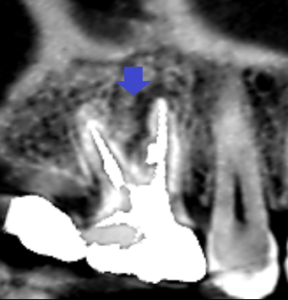

精密根管治療2年後後の経過観察時の

上顎大臼歯の矢状断のCT画像です。

矢印の先の根の先にあった膿の影が明らかに縮小し、

歯槽骨が再生してきています。

精密根管治療2年後の経過観察時の

上顎大臼歯の冠状断のCT画像です。

矢印の先に近心頬側根をとり巻くようにあった大きな膿の影が縮小し、